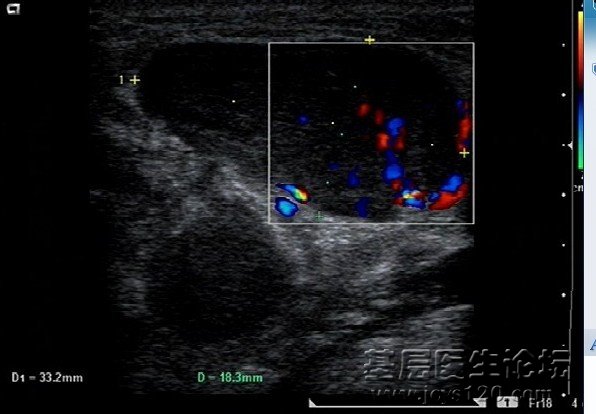

• 双侧脑室间占位? attach_img

• sxmz 2013-3-11

• 今日接诊一老年患者,因为下肢无力,活动不灵活一周入院,行颅脑CT检查,报告上有这么一个描述:双侧脑室间示类圆形低密度影,边界不清,CT值17HU 我上传一下片子,小斑竹给看下,我拍照的是否描述的层面 ...  阅读全文>